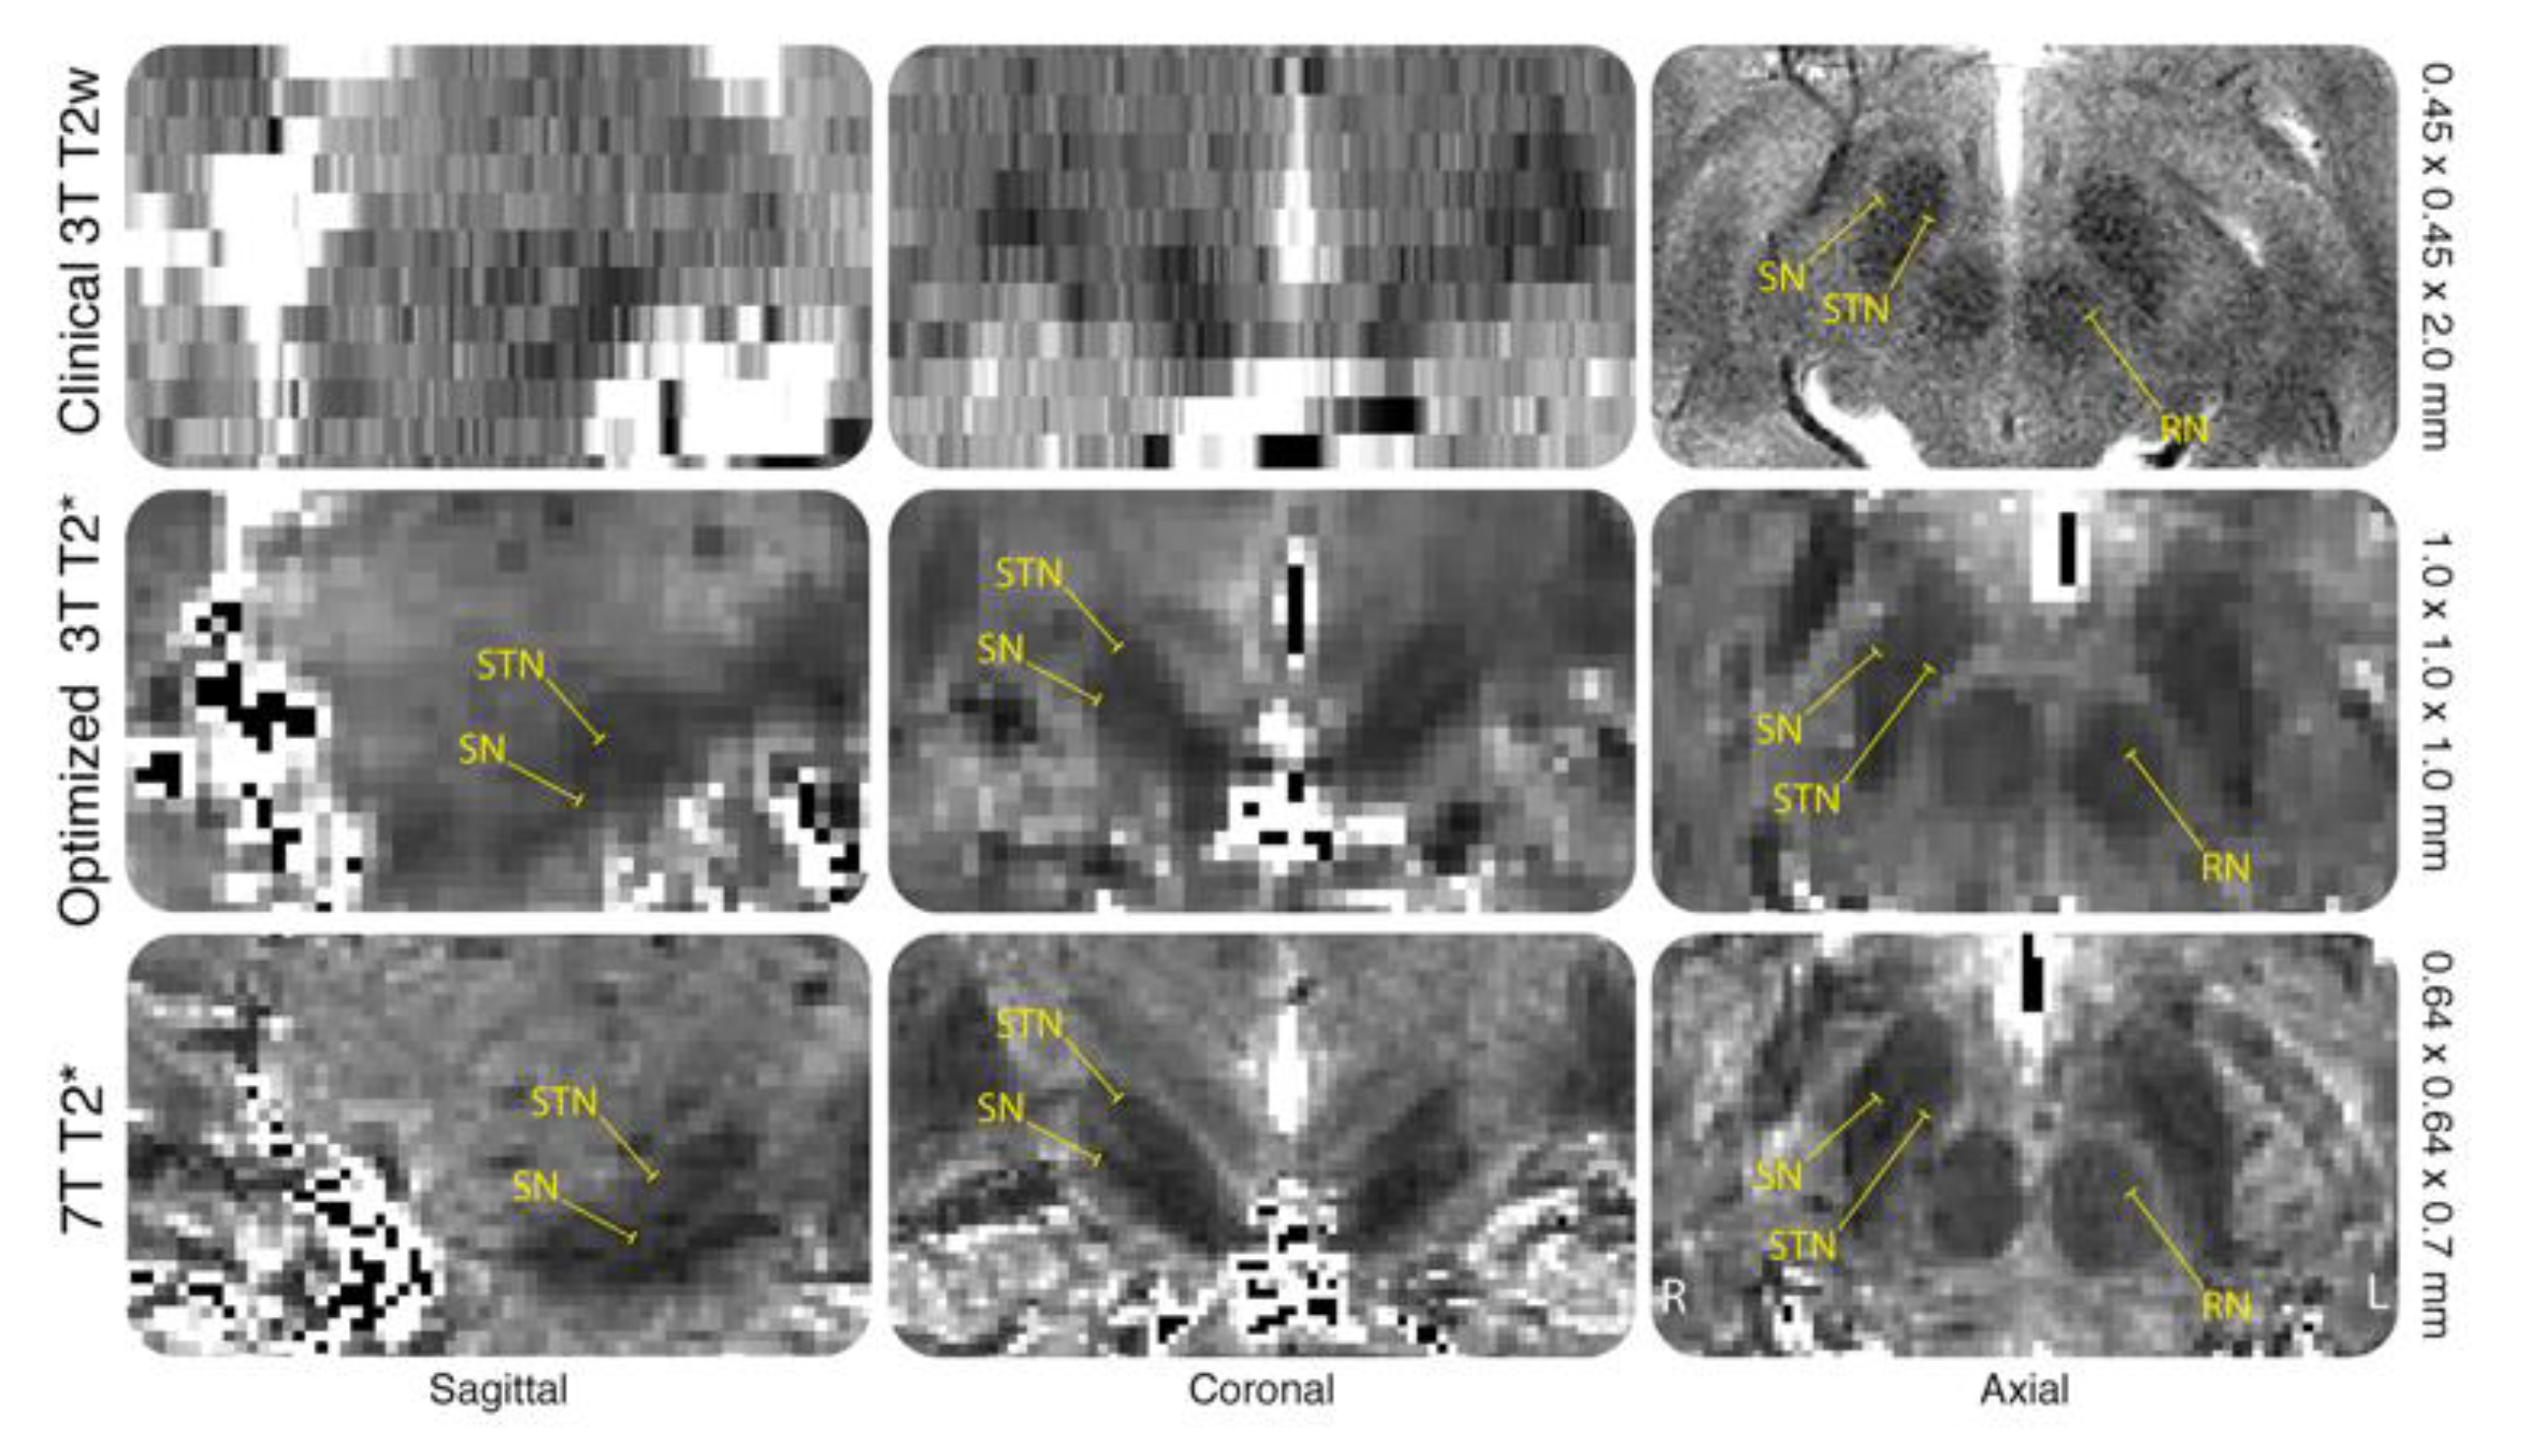

- Bot, M.; Verhagen, O.; Caan, M.; Potters, W.; Dilai, J.; Odekerken, V.; Dijk, J.; De Bie, R.; Schuurman, R.; Munckhof, P.V.D. Defining the dorsal STN border using 7.0-Tesla MRI: A comparison to microelectrode recordings and lower field strength MRI. Brain Stimul. 2019, 97, 587. [Google Scholar] [CrossRef]

- Kerl, H.U.; Gerigk, L.; Pechlivanis, I.; Al-Zghloul, M.; Groden, C.; Nolte, I. The subthalamic nucleus at 3.0 Tesla: Choice of optimal sequence and orientation for deep brain stimulation using a standard installation protocol: Clinical article. J. Neurosurg. 2012, 117, 1155–1165. [Google Scholar] [CrossRef]

- Mulder, M.J.; Keuken, M.C.; Bazin, P.L.; Alkemade, A.; Forstmann, B.U. Size and shape matter: The impact of voxel geometry on the identification of small nuclei. PLoS ONE 2019, 14, e0215382. [Google Scholar] [CrossRef]